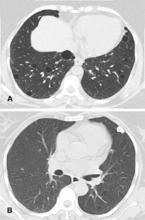

肺鈣化灶肺炎性鈣化CT表現(圖3):淋巴細胞性間質性肺炎。軸向 CT 顯示(肺窗):多發囊腫伴部分實質結節;圖 b 左肺外周可見鈣化結節;活檢證實為澱粉樣變。